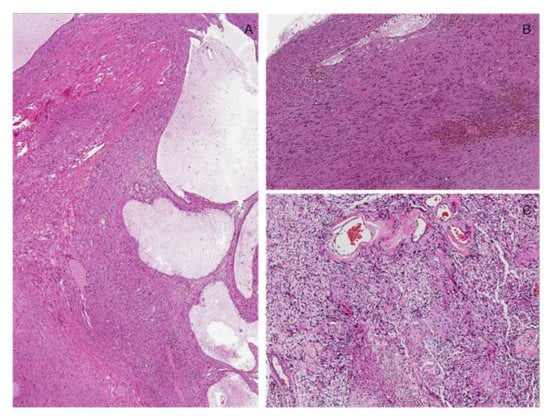

10. Malignant Melanotic Schwannian Tumor (So-Called “Melanotic Schwannoma”)

Molecular Features